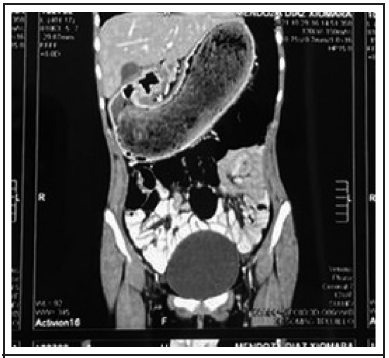

Mujer de 13 años de edad procedente de Moche, ocupación estudiante, grado de instrucción: 1º grado de secundaria. Rendimiento alto. Tres días antes del ingreso: paciente presenta dolor abdominal tipo cólico con intensidad 5/10 según Escala Visual Analógica (EVA), en región epigástrica sin irradiación. Dos días antes del ingreso: ante persistencia de dolor acude a médico particular quien le indica Tomografía Axial Computarizada (TAC) abdominopélvica y le administra metamizol 760 mg. endovenoso. El día del ingreso por emergencia acude con resultado de TAC abdominopélvica que informa “neumatosis gástrica con distensión de la cámara” (Figura 1) y con resultado de ecografía abdominal que informa: “formación hiperecogénica ocupante de cavidad gástrica hasta la región del antropíloro sugestivo de bezoar (tricobezoar)”. Se realizó: SARS-COV 2 (-) Grupo Sanguíneo O (+).

“Es imposible el diagnóstico con una radiografía simple, ya que los bezoares no son radiopacos; se pueden observar como una imagen heterogénea moteada que podría ser confundida con un estómago lleno. En el ultrasonido se destaca una banda aumentada de ecogenicidad en la región de estómago con pérdida completa de los ecos posteriores. Mediante la TAC con contraste es posible realizar el diagnóstico en el 97% de los casos (como en nuestro caso), en donde se puede observar un defecto de llenado”.10,12 La endoscopia fue determinante ya que permitió saber la naturaleza del cuerpo extraño.10,12 Las complicaciones más comunes son: erosión de la mucosa gástrica, ulceración, perforación, obstrucción, intususcepción, ictericia obstructiva, enteropatía por pérdida de proteínas, pancreatitis y muerte.13 Dada la enorme masa compacta que ocupaba toda la cavidad gástrica, el tratamiento necesitaba ser netamente quirúrgico, lo cual se hizo mediante incisión mediana supraumbilical que tuvo que ampliarse a infraumbilical. “Aunado al tratamiento quirúrgico, los pacientes deben iniciar también manejo psiquiátrico para el trastorno asociado” de ansiedad o depresión y “para disminuir el riesgo de recurrencia, sugiriendo su control hasta la estabilización psicológica”.10